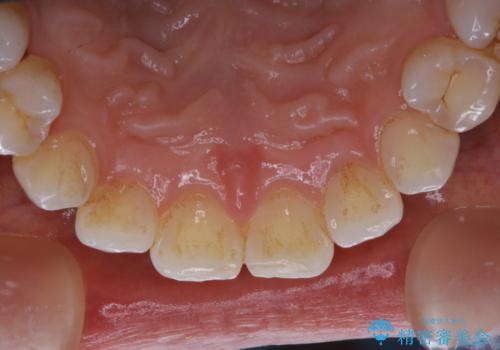

PMTCで見た目を綺麗に

- 専門的な機械ででしっかりとキレイにクリーニングしてほしいとのことでしたPMTC60分コースを行いました。

PMTCは、歯に付着した汚れを除去していくため、着色が気になる場合にも行うことができます。ご自身でのセルフケアだけで着色を落とそうとすると、逆に歯を傷つけてしまったり、精密に汚れを除去できないこともあります。また、日常生活で着色しやすい飲食物を避けたりすることはストレスに感じてしまったり、あまり現実的ではありません。

毎日丁寧に歯磨きをしていても、日常生活での飲食物などにより着色してしまうことはあります。PMTCでは、歯の表面の凸凹にミネラルを補給して、ツルツルの表面に仕上げます